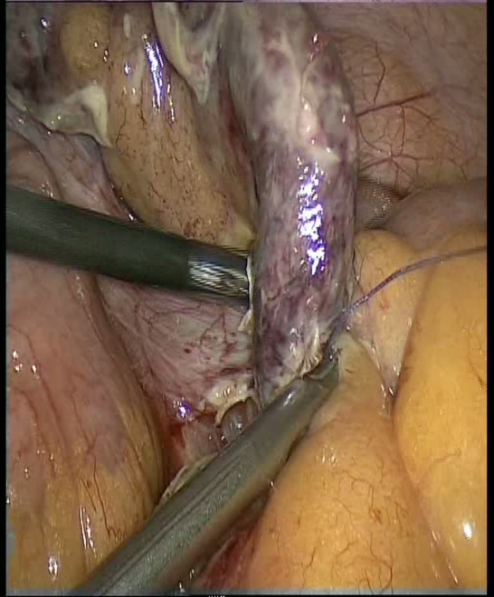

- Laparokopik appendektomiya ən çox tövsiyə olunan üsuldur, həm ağırlaşmamış, həm ağırlaşmış appendisitlərdə, hətta hamilələrdə aparıla bilər. Qadınlarda və diaqnostik çətinlikdə laparoskopiya ilk seçim sayılır.

- Əməliyyatdan əvvəl tapılan appendikulyar abseləri USM və ya KT nəzarərti altında dəridən keçən və ya cərrahi drenajla müalicə etmək olar. Əməliyyat vaxtı təyin edilən abseslərdə bitişmələr ayrılır, irin təmizlənir, mümkünsə appendektomiya edilir. İltihablaşmış piylik və piy artımları rezeksiya olunur. Abses bölgəsi və çanaq drenajlanır. Appendiks lizisə məruz qalıbsa, əməliyyat abses boşluğunun drenajı ilə tamamlanır.

- Təcili əməliyyat mütləqdir və peritonitin müalicəsi həyata keçirilir: laparotomiya/laparoskopiya, mənbənin aradan qaldırılması, sanasiya, drenaj, infuziya, antibiotikoterapiya, digər dəstək müalicələri.